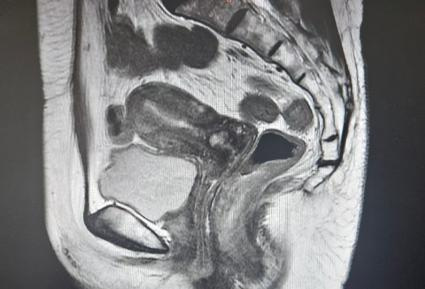

辅助检查:盆腔MRI:子宫内膜不规则增厚,局部T2WI低信号结合带连续性中断,增强后呈不均匀强化,与肌层分界不清,宫颈未见受侵。

诊断:子宫内膜癌

手术方式:腹腔镜经腹筋膜外全子宫切除术+腹腔镜下盆腔淋巴结清扫术+腹腔镜双侧卵巢输卵管切除术。

术后病理:子宫考虑子宫内膜样腺癌,I级,浸润深度5mm,侵及子宫肌层<1/2,未见神经及脉管侵犯,宫颈黏膜慢性炎,双侧输卵管卵巢未见明显病变,左盆腔淋巴结0/17,右盆腔淋巴结0/13。